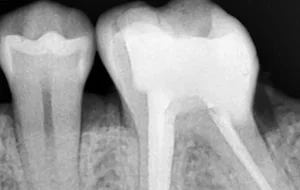

• Clean and disinfected canals are then sealed and filled with an inert rubber-like filling material known as Gutta-Percha.

• The very last step is restoration & crown. The crown portion of the tooth cavity is then restored with a filling, followed by a Cap/Crown cementation.